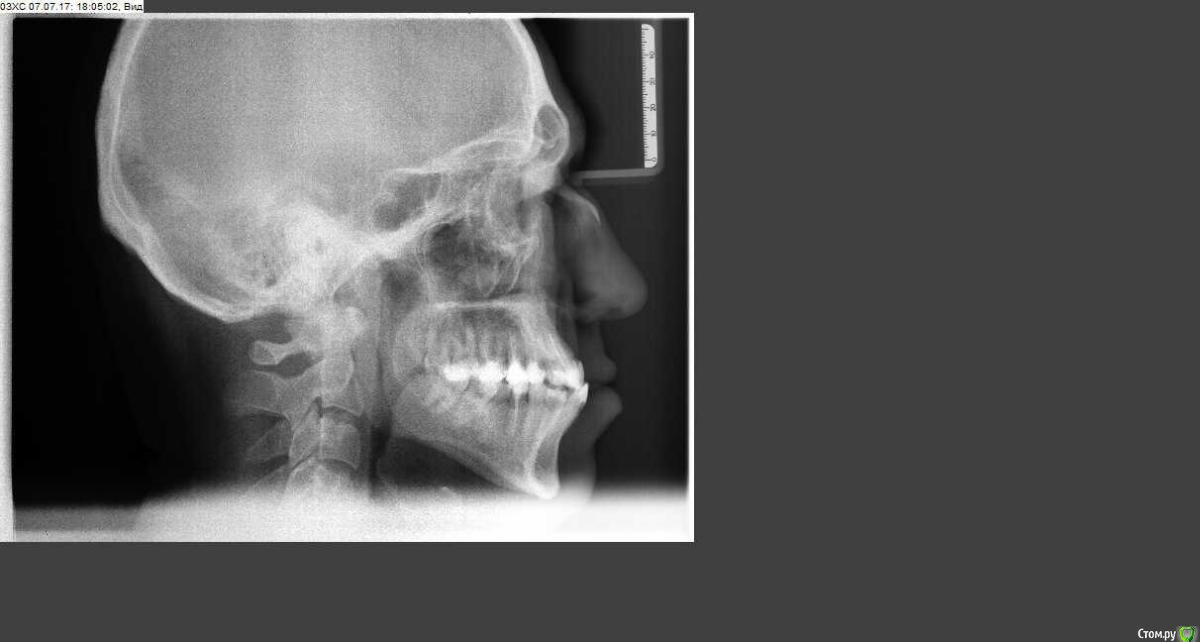

Мне 34 года, прикус мезиальный, наследственный. Решил исправить прикус. Есть нюанс по состоянию зубов, единицы, двойки, четверки и пятерки - коронки из композитного материала (световая пломба), после решения вопроса прикуса планирую заняться протезированием. Сходил к ортодонту, посоветовали съездить в Екб на консультацию в УГМУ. Съездил на консультацию, сказали что только операция с ортодонтической подготовкой до и после операции. При этом сказали, что удалять ничего не надо.